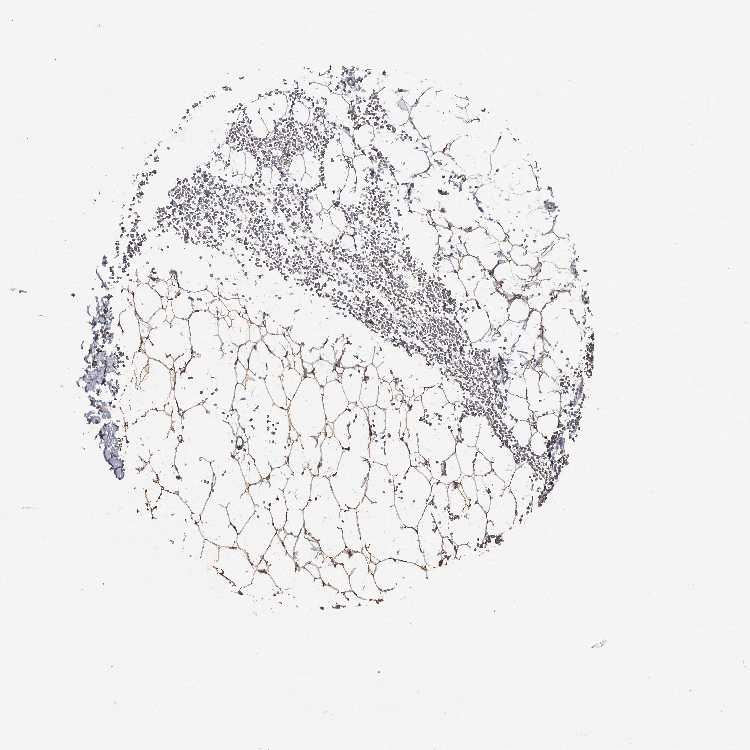

SOFT TISSUE 1 - Antibody stainingi

Antibody staining in the annotated cell types in the current human tissue is reported as not detected, low, medium, or high, based on conventional immunohistochemistry profiling in selected tissues. This score is based on the combination of the staining intensity and fraction of stained cells.

Each image is clickable and will lead to virtual microscopy that enables deeper exploration of all samples and also displays staining intensity scores, fraction scores and subcellular localization as well as patient and tissue information for each sample.

Antibody HPA007493Antibody CAB037230

Chondrocytes Low-

Fibroblasts Not detectedMedium

Peripheral nerve -Low

SOFT TISSUE 2 - Antibody stainingi

Chondrocytes -Medium